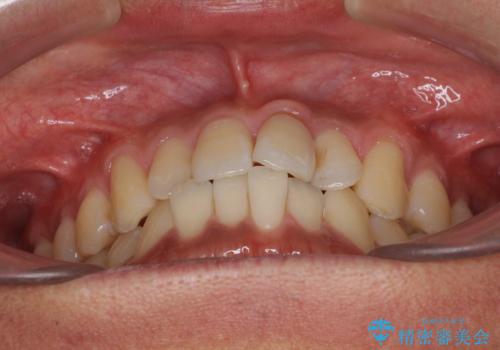

気になる前歯のデコボコをインビザラインで解消

- 前歯のデコボコを気にして来院された患者様です。

主に下顎歯列全体の後方移動とIPR(歯と歯の間を削る)によってデコボコが解消するように設計し、インビザラインにより治療を行うこととしました。

インビザライン矯正特有の、治療後半で前歯のみが強く接触する症状が発現し、咬み合わせ改善に期間を要することとなりました。